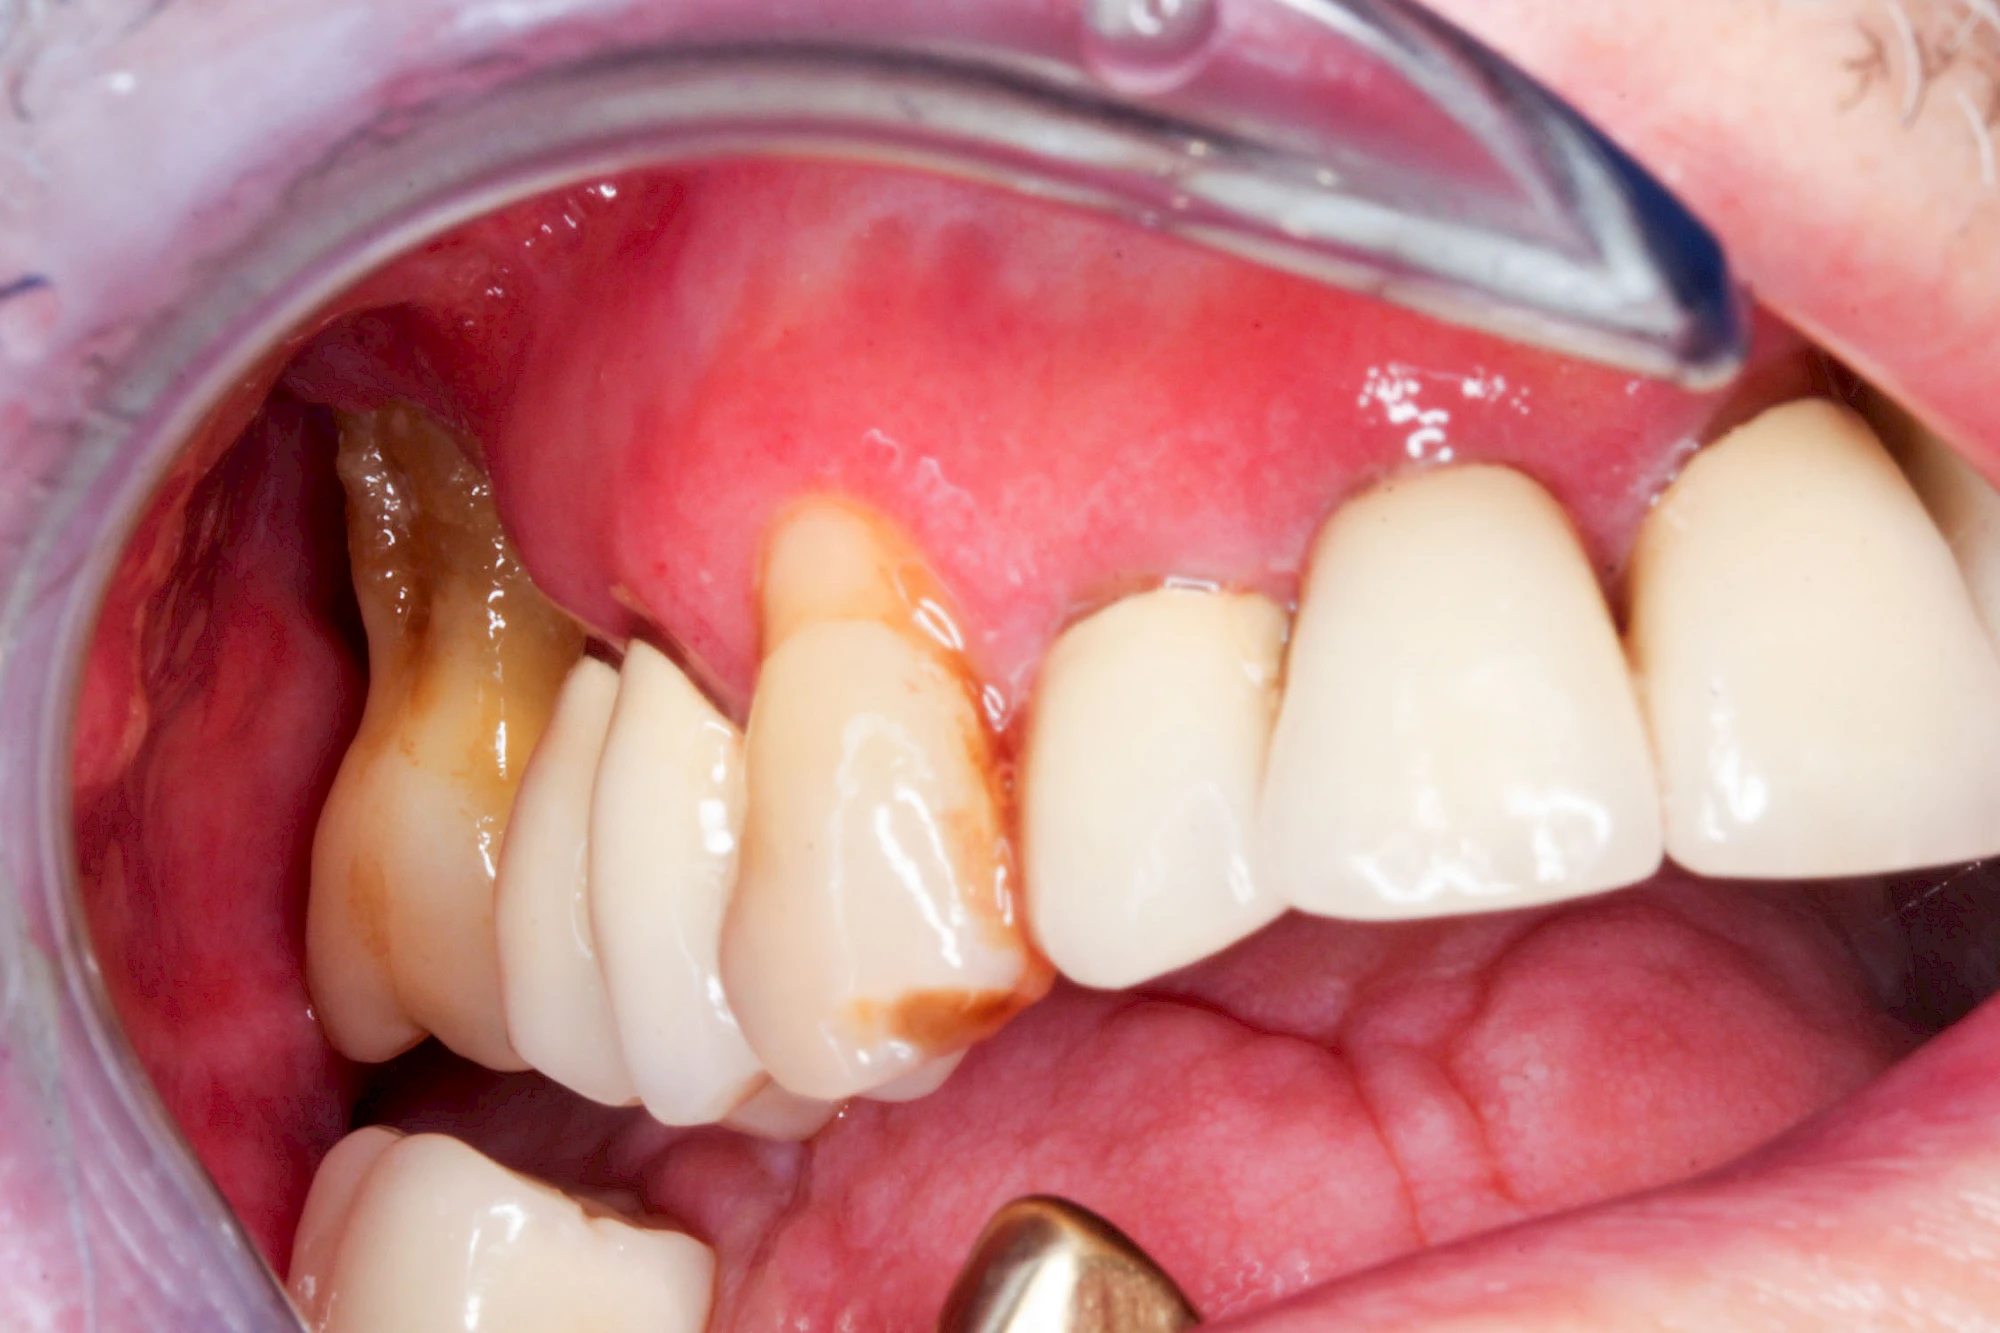

Ist zunächst nur das Zahnfleisch von der Entzündung betroffen, spricht man von Gingivitis. Später, wenn auch der Knochen um die Zähne herum entzündet ist, spricht man von einer Parodontitis. Bei der Parodontitis wird der Knochen nach und nach abgebaut und das Zahnfleisch zieht sich zurück. Die Zahnhälse und Zahnwurzeloberflächen liegen mehr und mehr frei. Die Zähne werden zunehmend lockerer und fallen schließlich aus.

Bei einer Fistel hat sich meist eine Entzündung (manchmal auch Erreger selbst) z. B. aufgrund von Karies oder aufgrund eines Unfalls über den Zahnnerv und die Wurzelspitze (Apex) in den umliegenden Knochen ausgebreitet (apikale Parodontitis) und schnell einen Weg durch den umgebenden Knochen und die aufliegende Schleimhaut in die Mundhöhle gebahnt.

Fisteln sind in der Regel nicht schmerzhaft und fallen häufig als kleine Öffnung weiter entfernt vom Zahnfleisch nahe der Umschlagfalte auf. Aus der Fistelöffnung entleert sich spontan gelbliches Sekret (Eiter) oder es lässt sich mit dem Finger ausstreichen. Manchmal beschreiben die betroffenen Menschen immer wieder einen komischen Geschmack im Mund.

Im fortgeschrittenen Stadium kann die Schleimhaut sich weiter zurückgezogen haben und die Wurzelspitze sichtbar sein. In der Regel treten bei Fisteln keine Schwellungen auf, weil sich die Entzündung nicht im Gewebe ausbreitet.